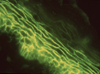

Pemphigus foliaceus is an acquired autoimmune blistering disease in which the body's immune system produces IgG autoantibodies that target the intercellular adhesion glycoprotein desmoglein-1, which is principally expressed in the granular layer of the epidermis, resulting in the loss of intercellular connections between keratinocytes (acantholysis) and the formation of subcorneal blisters within the epidermis. This article summarizes the epidemiology, clinical features, techniques for diagnosis, and drugs associated with treatment of this rare disease.